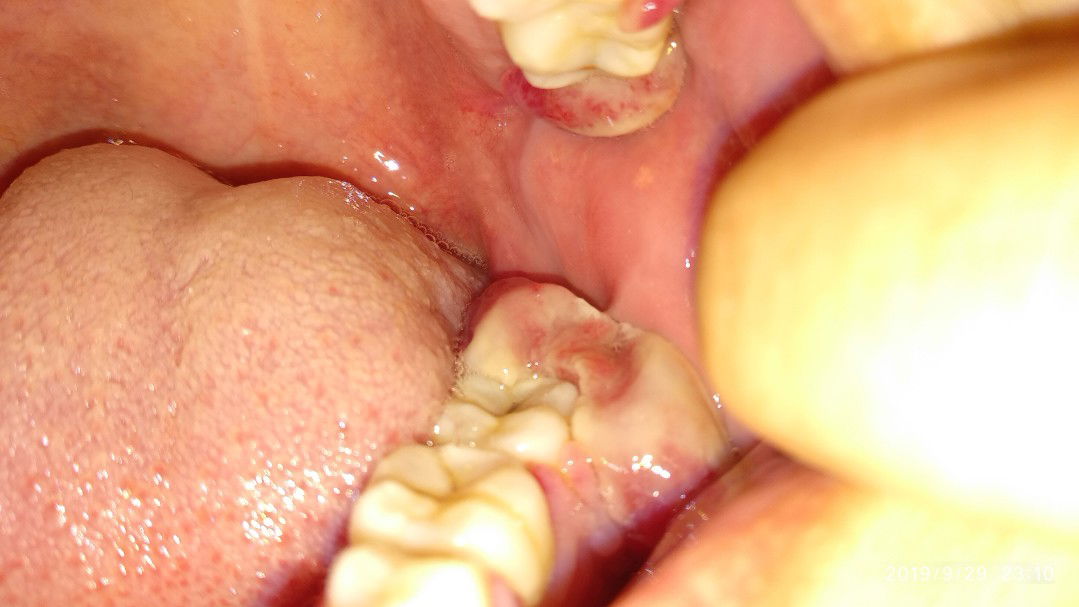

gusi bengkak

Hai mommies smua,ada x yg sama sakit mcm sy?n ada pnyelesaiannya x?gusi bgkak start pregnant,makin teruk bila msuk 5bulan..sy dh pergi refer klinik gigi,tp doktor x blh buat apa just sruh beli ubat kumur,sbb sy tgh mngandung ktanya..skrg gusi blkg ats n bwh dh bgkak teruk..